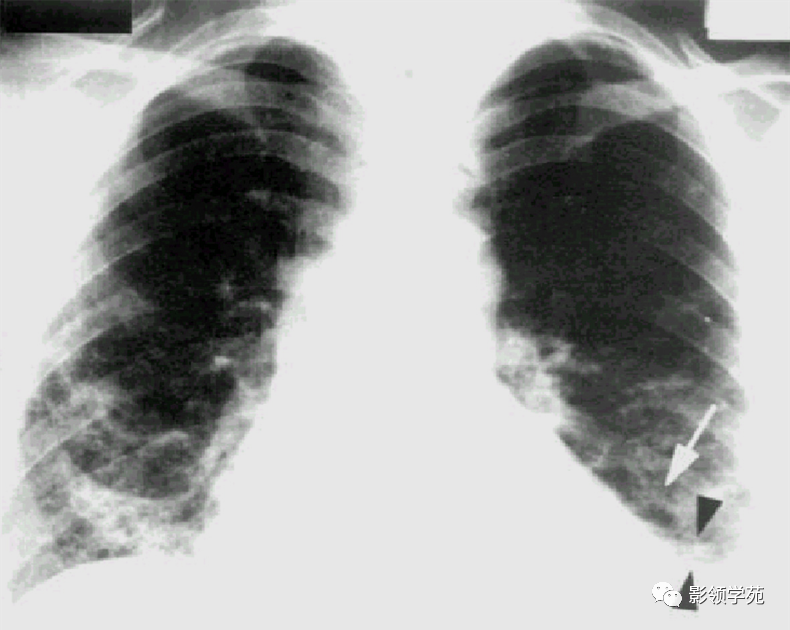

瘤外科患者,女,48岁,左乳癌根治术后2月术后化疗。病理:左乳伴髓样癌特征的乳腺浸润性导管癌。术后TAC方案化疗1个周期。

左乳切除术后,左肺下野两个大小不等高密度影。